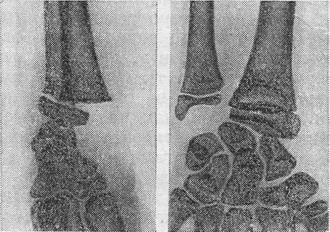

![]() Рис. 6. Перелом за типом «зеленої гілки». Рис. 7. Поднадкостнічний перелом ліктьової кістки. |

![]() Рис. 8. Епіфізеоліз променевої кістки зі зміщенням. |

Особливості у будові кісток у дітей зумовлюють переломи, властиві тільки дитячому віку. До таких відносяться надломи або переломи за типом «зеленої гілки» (рис. 6), а також поднадкостничные переломи, коли зламана кістка залишається вкритою непошкодженій окістям (рис. 7). Відламки в цих випадках зміщуються незначно. Тільки у дітей і підлітків зустрічаються такі види переломів, як эпифизеолизы, коли відбувається відрив епіфіза по лінії паросткового хряща, епіфіз при цьому відділяється від метафіза і зміщується (мал. 8). За механізмом травми эпифизеолизы подібні вивихів у дорослих і відбуваються в тих кістках, де суглобова сумка прикріпляється до эпифизарному хряща (нижній кінець стегнової кістки, променевозап'ястний і гомілковостопний суглоби). Клінічні ознаки переломів у дітей загалом аналогічні тим, які спостерігаються у дорослих, а у дітей часто відзначається значне підвищення температури у перші дні після травми. Діагностика представляє труднощі при поднадкостничных переломах та при эпифизеолизах без зміщення, а також з-за поганого контрастування на рентгенограмах хрящової тканини епіфіза у маленьких дітей. Зрощення переломів у дітей завдяки доброму кровопостачанню кістки і окістя відбувається значно швидше, ніж у дорослих. Лікування визначається видом перелому і віком дитини. Більшість переломів лікують фіксуючою пов'язкою у вигляді гіпсової лонгети, яка повинна захоплювати 2/3 окружності кінцівки і два суміжних суглоба вище і нижче місця перелому. Лонгета фіксується марлевим бинтом. Циркулярні гіпсові пов'язки у дітей не застосовують із-за великої небезпеки порушення живлення кінцівки. При наявності зміщення відламків перед накладенням лонгет необхідно домогтися їх зіставлення. При репозиції уламків слід особливо ретельно виправляти кутові зміщення. Найчастіше застосовується одномоментна ручна репозиція під наркозом. При переломі стегнової кістки і кісток гомілки зі значним зміщенням застосовують витягування, яке у дітей грудного і ясельного віку здійснюється за допомогою липкого пластиру чи клеола. У більш старших дітей при переломі стегнової кістки накладають скелетне витягання за спицю, проведену через проксимальний метафиз великогомілкової кістки або дистальний метафиз стегнової.